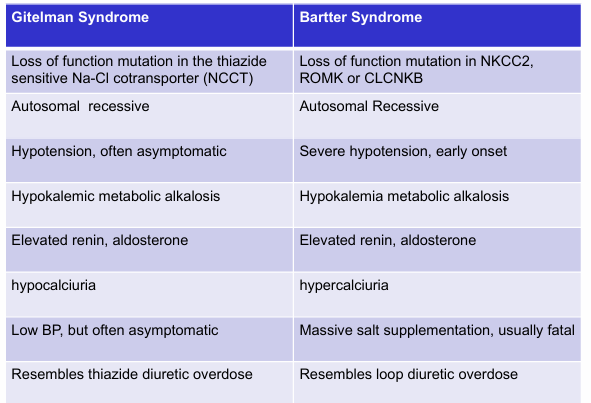

hypotensive disorders with hypokalemic metabolic alkalosis- Gitelman syndrome, Bartter syndrome